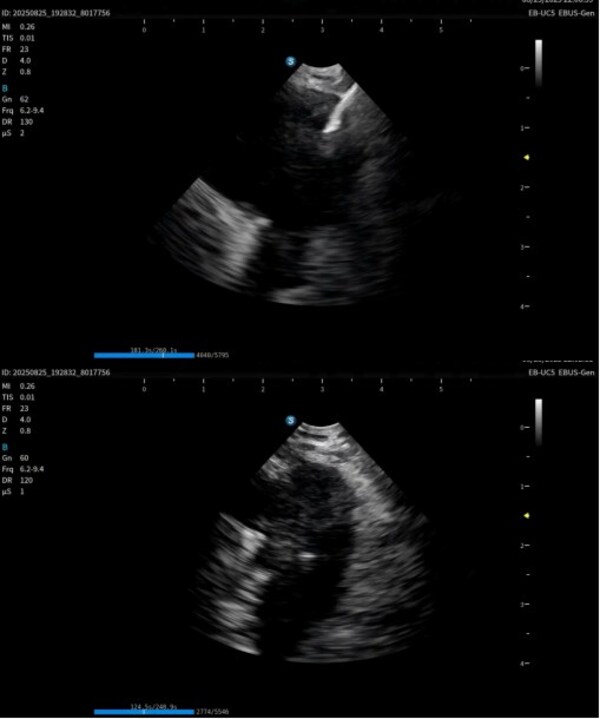

作為在呼吸診療領域的重磅產品,本次在產品創(chuàng)新設計上和工藝技術上取得了重大突破,顯著提升了光學圖像和超聲圖像的質量,同時鏡體保持了良好的操作性,在鉗鏡比和視野角綜合參數可達到全球同類產品最佳性能。目前在臨床應用表現突出,取得了專家的認可和好評。

超聲電子支氣管內窺鏡憑借其"微創(chuàng)、精準、安全"的特點,已成為呼吸介入領域的核心技術之一。開立醫(yī)療全系列產品全面上市可為肺部腫瘤、縱隔病變提供管內清晰光學影像,管外高清聲學斷層組織及血流影像,提供精準可視化介入操作,為疾病的診斷提供更精準、更安全、更高效的一體化診療解決方案。